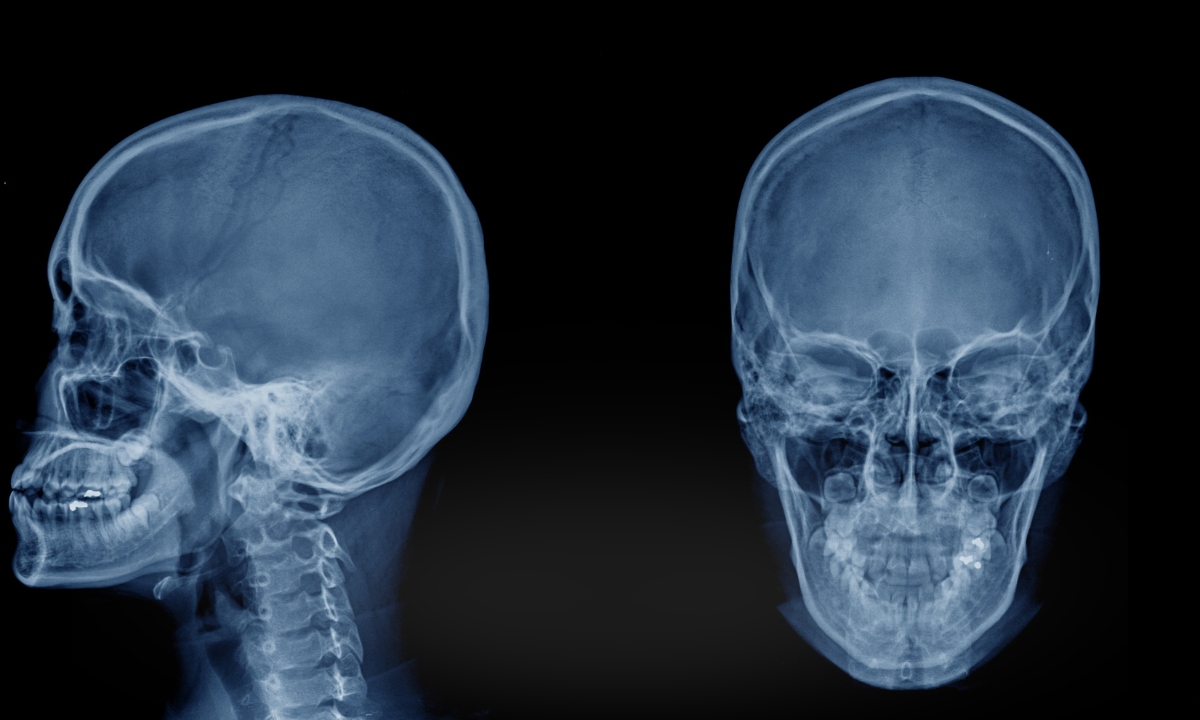

A sigla ATM significa articulação temporomandibular. Essa articulação conecta a mandíbula ao osso temporal do crânio, localizado na lateral da cabeça, próximo ao ouvido.

A articulação temporomandibular está localizada na lateral da face, próxima ao ouvido. Essa estrutura conecta a mandíbula ao crânio e permite que os movimentos da boca ocorram de forma coordenada.

Cada pessoa possui duas ATMs, uma de cada lado da cabeça. Essas articulações funcionam de forma sincronizada para que a mandíbula possa se movimentar corretamente durante atividades como falar ou mastigar.

A ATM é considerada uma das articulações mais complexas do corpo humano, pois combina diferentes tipos de movimento e depende da ação conjunta de músculos, ligamentos e do disco articular.

Localização da articulação temporomandibular

A ATM fica localizada logo à frente da orelha, na lateral da face.

Em alguns casos, exames de imagem podem ser utilizados para avaliar a articulação temporomandibular.

Entre eles estão radiografia, tomografia computadorizada e ressonância magnética.